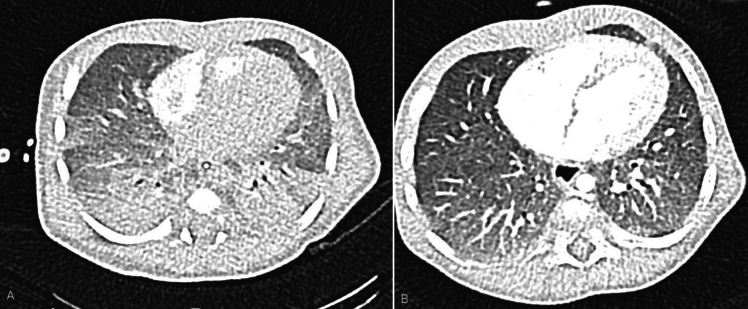

Results: We reported three off-label cardiorespiratory reasons to use IL-1Ra from our series: (i) chronic lung disease with pulmonary hypertension, (ii) interstitial lung disease with pulmonary hypertension to facilitate the weaning from respiratory support, and (iii) post-surgical polyserositis if effusions accumulate despite drainage. In all our patients, the drug was administered at a dosage of 10 mg/kg/day. The route of administration was chosen based on the patient's clinical characteristics, with the subcutaneous and intravenous routes being comparable in efficacy. The duration of therapy was modulated based on the patient's clinical response, with a minimum duration of 4 months. A total of 308 retrieved articles were screened, and then full texts of records deemed eligible for inclusion were assessed. Based on the literature search and our five cases, a total of 17 infants were treated with anakinra outside its approved indications. The major off-label use was for hemophagocytic lymphohistiocytosis/macrophage activation syndrome, followed by multisystem inflammatory syndrome in children and Kawasaki disease, as in two of our cases.

背景:Anakinra是一种白细胞介素-1受体拮抗剂(IL-1Ra)。由于IL-1已被证明在不同自身炎症性疾病的病因学中发挥关键作用,阻断其通路已成为一个重要的治疗靶点,即使在新生儿中也是如此。目的:我们的目的是报告我们使用阿那白那治疗特定新生儿炎症的经验。方法:我们描述了自2020年起在意大利罗马Bambino Gesù儿童医院IRCCS新生儿重症监护病房(NICU)收治的5例新生儿或3个月以下婴儿的临床处理。从电子病历中收集新生儿重症监护病房住院的病史和临床资料。此外,我们对截止到2024年4月5日的前3个月的说明书外anakinra进行了文献综述。我们从本综述中排除了冷冻素相关周期性综合征、白细胞介素-1受体拮抗剂缺乏和甲羟戊酸激酶缺乏的病例,阿那白素是已知的治疗方法。结果:我们报告了本系列中使用IL-1Ra的三个非适应症心肺原因:(i)慢性肺部疾病伴肺动脉高压,(ii)间质性肺疾病伴肺动脉高压,以促进脱离呼吸支持,(iii)术后多浆膜炎,如果引流后积液积聚。在我们所有的患者中,给药剂量为10mg /kg/天。根据患者的临床特点选择给药途径,皮下给药途径和静脉给药途径疗效相当。治疗的持续时间根据患者的临床反应进行调整,最小持续时间为4个月。总共筛选了308篇检索到的文章,然后评估被认为符合纳入条件的记录的全文。根据文献检索和我们的5例病例,共有17名婴儿在其批准的适应症之外接受了阿那金那治疗。主要的适应症外使用是用于噬血细胞淋巴组织细胞增多症/巨噬细胞活化综合征,其次是儿童多系统炎症综合征和川崎病,如我们的两个病例。结论:根据我们的病例系列和文献回顾的结果,可以考虑在一线治疗难治性炎症的新生儿中超说明书使用阿那白拉。有必要进行前瞻性的多中心研究,以确定anakinra是否是这些婴儿预防早期炎症性疾病的安全治疗选择,以及在哪些情况下它可以提高临床结果。